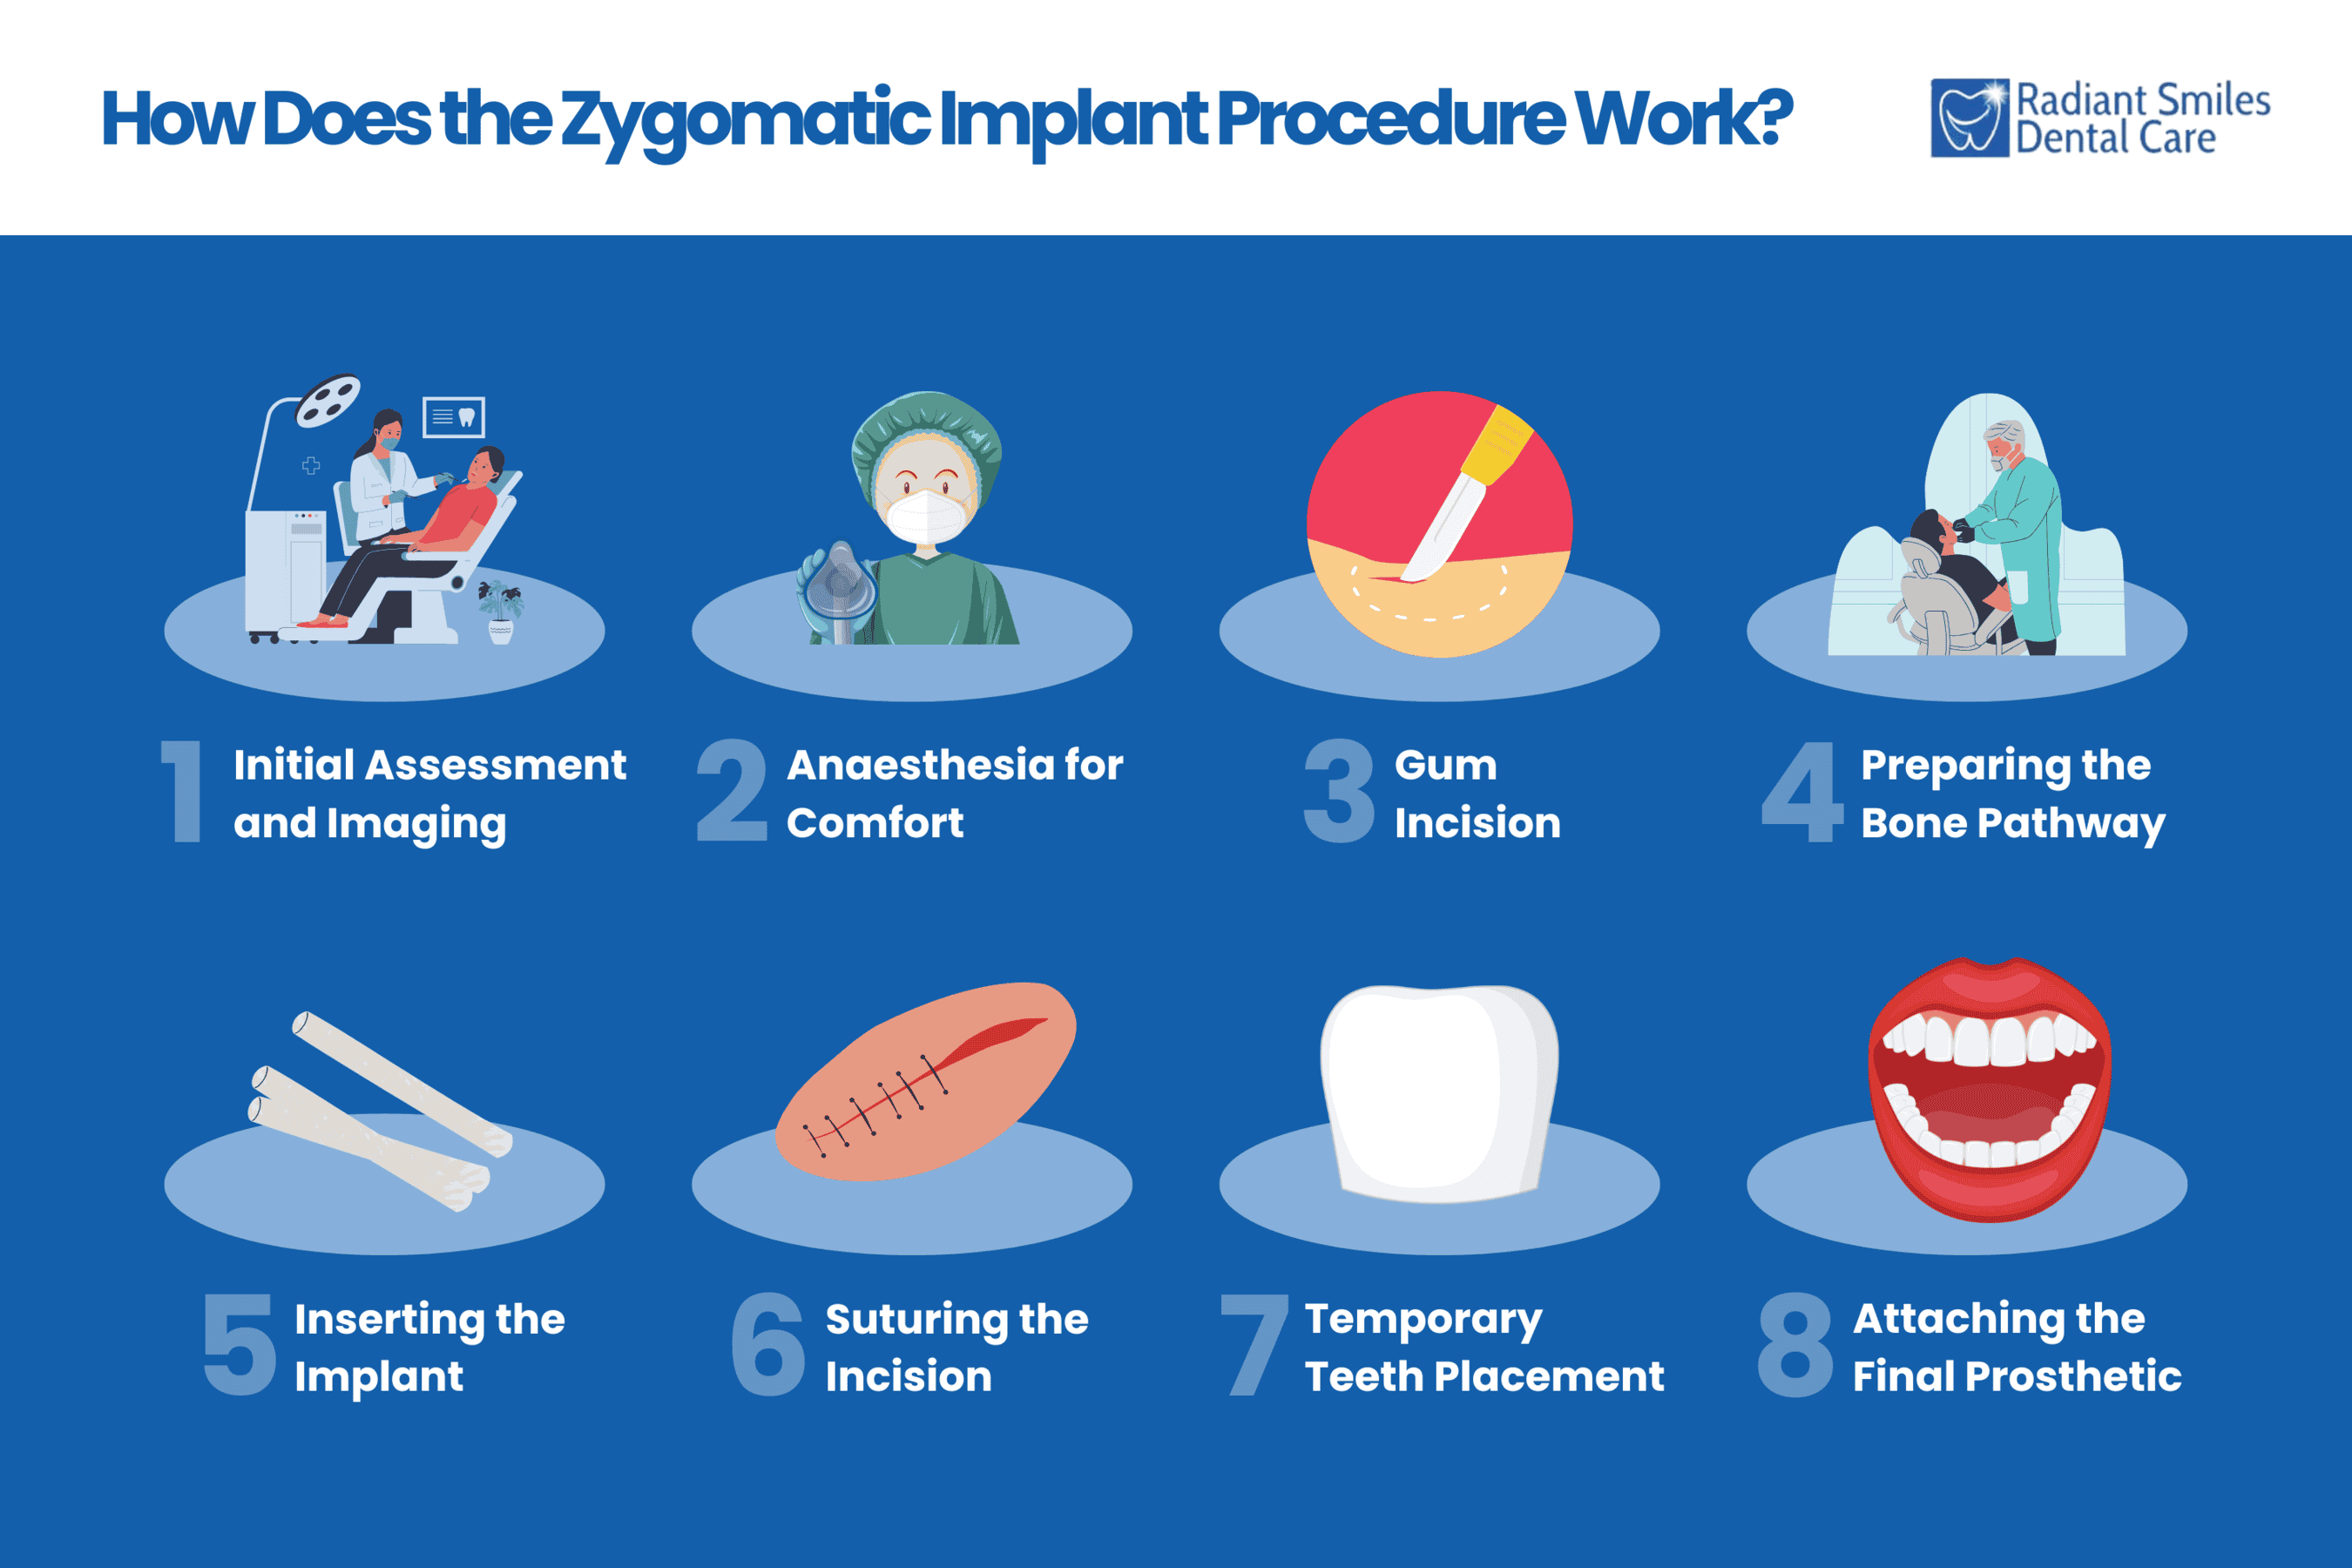

How does the Zygomatic Implant Procedure Work?

The zygomatic implant procedures involve careful planning, precise placement of implants into the cheekbone, securing temporary teeth soon after surgery, and fitting permanent restorations once healing is complete.

The zygomatic implant procedures involve careful planning, precise placement of implants into the cheekbone, securing temporary teeth soon after surgery, and fitting permanent restorations once healing is complete.

1. Initial Assessment and Imaging

The process starts with a thorough evaluation, including 3D imaging, to assess the bone structure and determine the best positions for implant placement. This planning avoids important oral and maxillofacial structures like nerves and sinus cavities.

2. Anaesthesia for Comfort

Local anaesthesia, often combined with sedation, is used to keep the patient relaxed and free from pain throughout the procedure.

3. Gum Incision

A small incision is made in the gum to expose the bone. This step provides access for preparing the implant site.

4. Preparing the Bone Pathway

The surgeon carefully drills an angled pathway from the upper jawbone to the zygomatic bone using specialised tools. This makes sure the implant has a secure and stable fit.

5. Inserting the Implant

The long zygomatic implant is placed into the prepared pathway and anchored in the cheekbone, providing stability in cases of significant bone loss.

6. Suturing the Incision

The incision is closed with sutures, protecting the site and initiating the healing process.

7. Temporary Teeth Placement

In many cases, a temporary prosthetic is attached to the implants shortly after surgery. This provides functional and aesthetic benefits while the implants heal.

8. Attaching the Final Prosthetic

After the healing period, during which the implants integrate fully with the bone (osseointegration), a customised, permanent prosthetic is fitted. This final restoration is designed for durability and a natural appearance